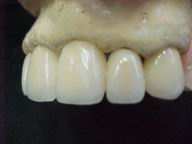

Reabilitação funcional e estética em ambas as arcadas

com próteses fixas e removíveis de encaixe de precisão.

Vista Oclusal Sobre Modelos de Gesso